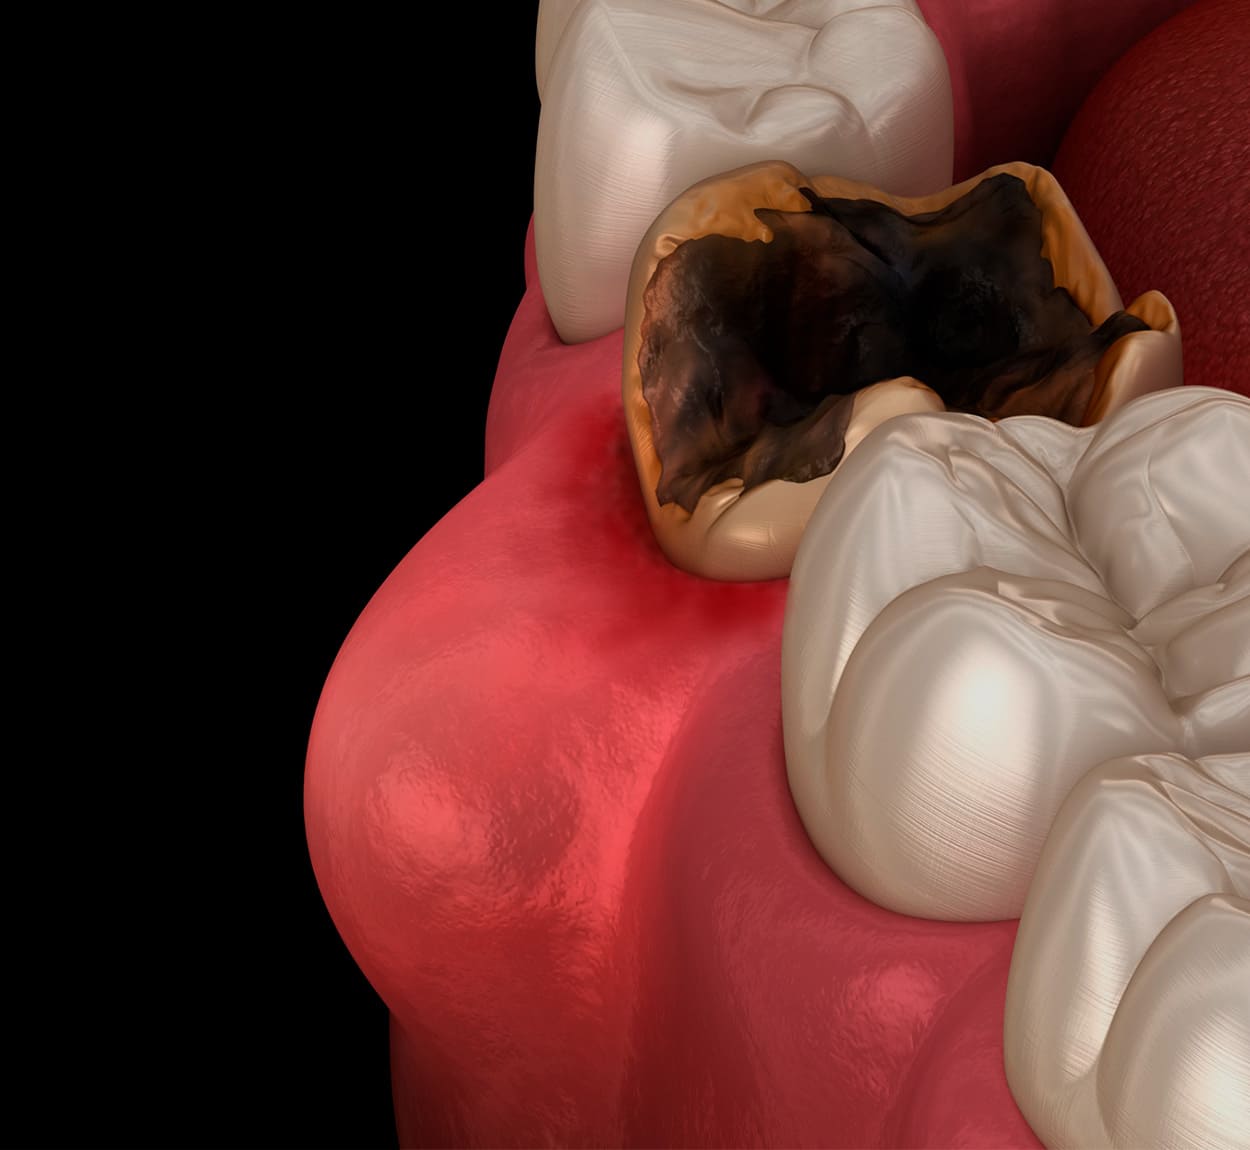

一般歯科

一般歯科は主に、虫歯治療や歯周病治療などが含まれます。

簡単な抜歯や入れ歯治療も一般歯科にあたります。口腔内の健康を維持するために必要な、予防治療から歯の治療が含まれるので、広範囲にわたる歯科治療を提供する分野として位置づけられています。マイクロスコープによる精密な治療により、歯の削る量は最小限に抑えることが可能です。

また、丁寧な麻酔で痛くない虫歯治療を提供します。